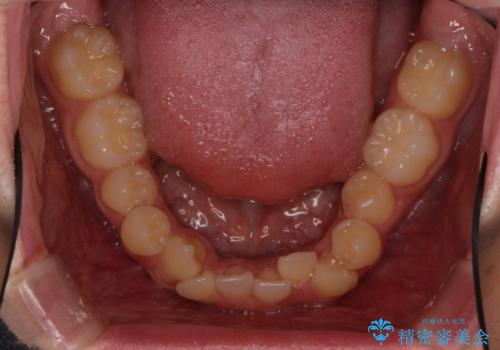

- 上下の八重歯や乱杭歯を気にして来院され患者様です。

スペースを確保するため、上下左右の小臼歯を抜歯し、ワイヤー装置に矯正することとしました。

奥歯の咬み合わせの左右差が大きかったため、変則的な抜歯矯正を行いました。

治療期間はやや長期化しましたが、満足のいく歯並びとなりました。